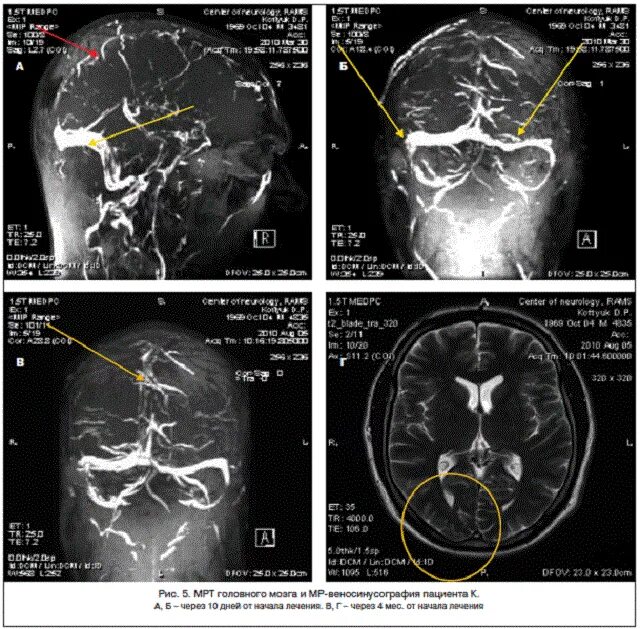

Синусы мозга мрт